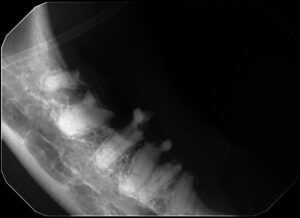

- Dental X-rays (radiographs) to evaluate the roots and structures below the gumline

Dental X-rays are essential because many lesions occur below the surface and cannot be seen during a routine awake exam.